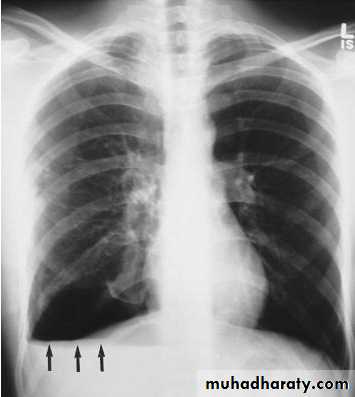

When fluid and air are present in the pleural space on an upright chest x-ray, a perfectly straight horizontal line will extend all the way from the spine to the edge of the pleural cavity. In this patient, a loculated right basilar hydropneumothorax is present.The air/fluid interface is easily seen (arrows). If this were a lung abscess, the air/fluid level would be very unlikely to extend all the way from the medial to the lateral aspect of the hemithorax.